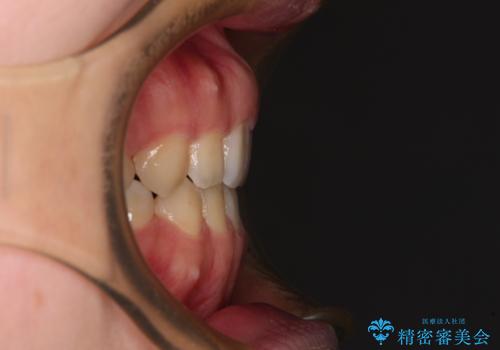

- 口元の膨らみが気になるとのことで来院された患者様です。

非抜歯で口元の突出感を少し改善させる治療も提案しましたが、最大限口元を引っ込めたいとのことでした。

上下左右第一小臼歯4本を抜歯し、ワイヤー装置により矯正治療を行うこととしました。